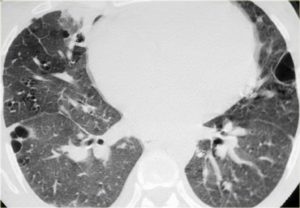

(Справа) На аксиальной КТ с КУ у этого же пациента визуализируются участки снижения пневматизации в виде «матового стекла» на фоне утолщения междольковых перегородок и участков низкой плотности («мозаичная» картина). «Матовое стекло»-неспецифический признакгипер-чувствительного пневмонита 1-й группы. Предположить этот диагноз помогает наличие других подозрительных признаков и симптомов. (Слева) На аксиальной КТВР у пациента с гиперчувствительным пневмонитом 1-го типа визуализируются центрилобулярные очаги с плотностью «матового стекла» с диффузным распределением. Видна также дольковая воздушная «ловушка». Центрилобулярные очаги «матового стекла» типичны для гиперчувствительного пневмонита 1 -й группы. Некоторые заболевания могут проявляться схожей картиной (например, респираторный бронхиолит).